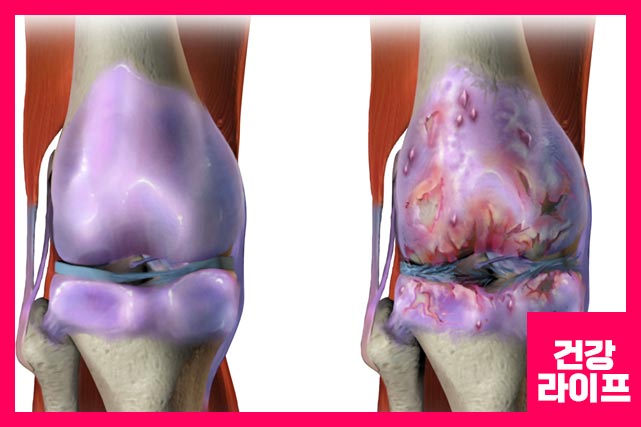

관절에는 얇은 막인 활막으로 둘러싸여 있으며, 관절 활막에 염증 반응이 지속적으로 나타난다면 류마티스 관절염이라고 말합니다.

관절은 뼈와 뼈를 연결하는 곳을 말합니다. 이 곳에 류마티스 관절염이 발생하면 연골 손상, 뼈 침식이 일어나면서 관절에 치명적인 손상이 일어나면서 더 이상 관절 기능을 제대로 할 수 없게 될 수 있습니다.